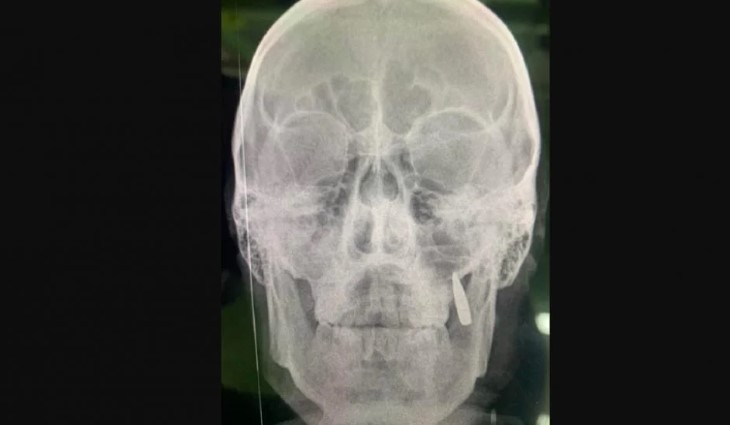

Волонтер показала рентгенівський знімок бійця, де видно кулю, яка застрягла у щелепі.

У бійця, якого привезли до стабілізаційного пункту поблизу передової, виявили кулю у щелепі замість зубів. Про це повідомила у Facebook народний депутат 8-го скликання, волонтер, громадський діяч Оксана Корчинська.

“Робимо рентген, замість двох зубів у щелепі застрягла куля. Ну так собі імплант”, – написала Корчинська.

Також вона показала рентгенівський знімок бійця, де видно кулю, яка застрягла у щелепі